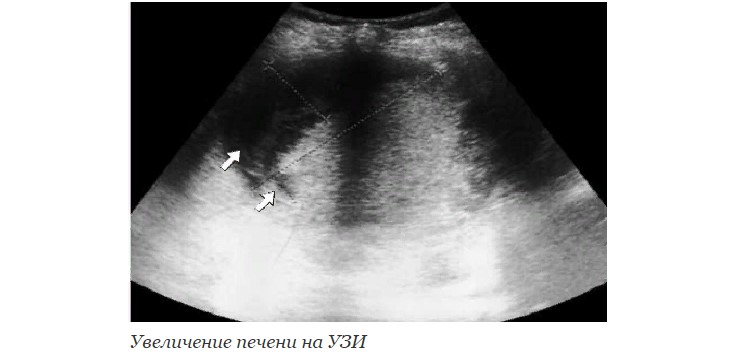

- УЗИ печени – это совершенно безболезненный способ, позволяющий идентифицировать размер органа, общее состояние паренхимы и кровотока, присутствие объемных формирований, параметры которых повышены.

Определив увеличение печени у ребенка по УЗИ, рекомендуется пройти дополнительные обследования.